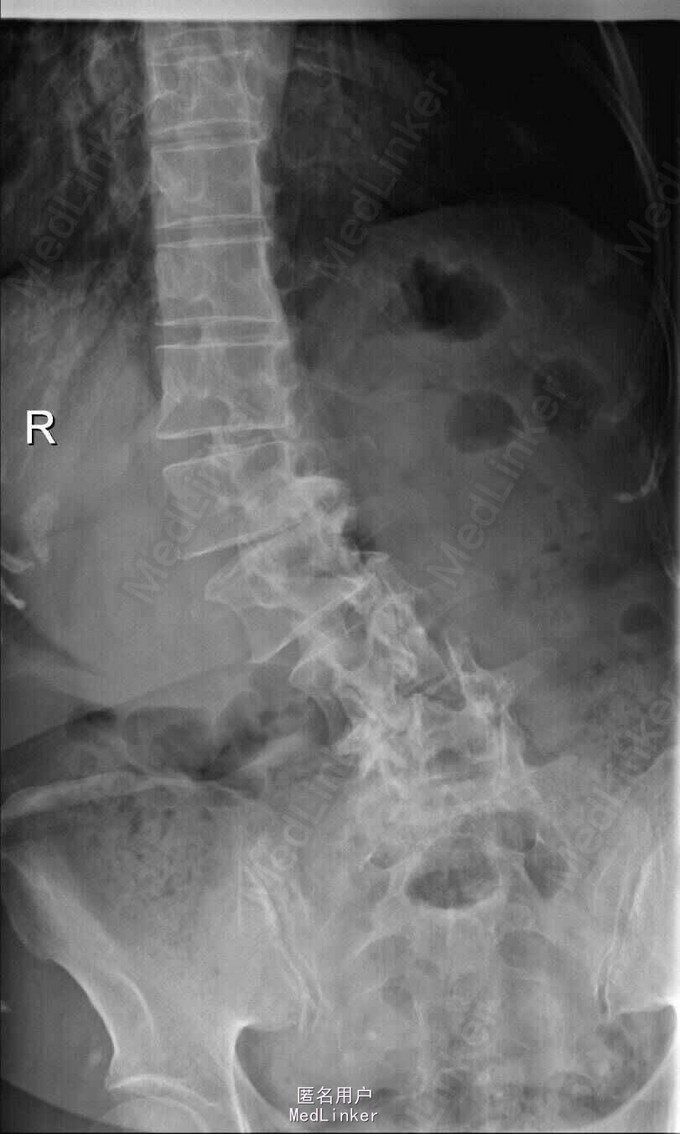

主诉:右下肢麻木伴驼背11年余 病史:患者女性,64岁,11年前无明显诱因出现右下肢疼痛,休息后好转。未予重视,后出现右下肢麻木感,逐渐小狐仙右臀部坚硬,驼背,伴跛行。常感双腿酸胀,腰部疼痛。自行步行距离小于200米,即会发生右下肢僵硬,麻木疼痛。X线检查示腰椎侧弯

查体:脊柱侧弯,上肢无麻木,疼痛感觉异常,腰部右侧疼痛,右下肢及右臀部疼痛,麻木感。双侧肌力及肌张力可,膝腱反射(+),踝反射(+),病理征(—),直腿抬高试验。右侧40度,左侧55度。 辅助检查:腰椎x线片:腰椎侧弯,腰椎退行性改变,L5椎体略行前滑脱 脊柱全长:胸腰段呈S形,L5椎体向前滑脱,L3椎体略变扁,颈胸腰椎退行性改变 MRI:脊柱侧弯,L2-3,L3-L4,L4-L5,L5-S1椎间盘突出,相应节段椎管狭窄